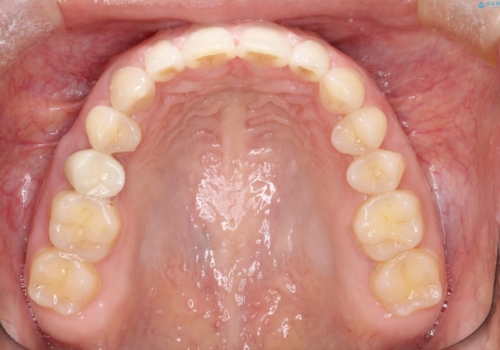

短期間での治療終了を希望され、ワイヤー矯正にて治療を行い1年ほどで治療を終了しております。

下顎前歯は矯正後補綴治療を行なっております。

期間や仕上がりで大変満足していただきました。

空隙歯列は後戻りしやすいため、長期間の保定が必要となります。